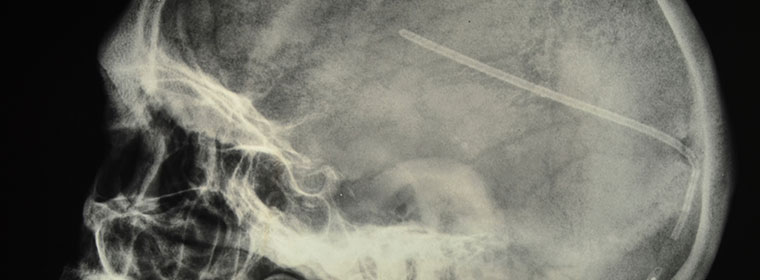

It is important to diagnose hydrocephalus before neurological damages occur. Hydrocephalus can be treated by eliminating the CSF block, by placing a surgically implanted shunt to divert the CSF to another body cavity or by a third ventriculostomy to shunt the CSF to another intracerebral space.